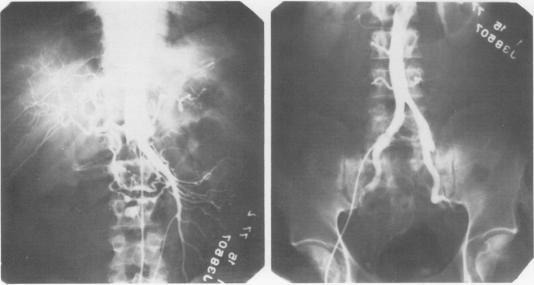

Thirty of 33 patients (ages 18-67) with acute dissection of the ascending aorta underwent surgical intervention. There were four deaths. There were eight male and five female patients and 15 patients were known to be hypertensive. Severe chest pain, widened mediastinum (demonstrated radiographically), and varying degrees of aortic insufficiency were present in each patient. Heart failure was present in 13 patients, numbness and coolness of an extremity in seven patients, and central nervous system changes were present in three patients. The diagnosis in each instance was confirmed by aortography. Three patients treated nonoperatively died during hospitalization following aortic rupture into the mediastinum and pericardium. The remaining 30 patients were managed by insertion of a woven Dacron((R)) graft sutured distal to the coronary arteries and proximal to the origin of the great vessels. This was accompanied with resuspension of the aortic valve in 24 patients and valve replacement in six patients. Each of the latter six patients had a history of aortic valve disease. The goals of the operation were: 1) correction of the accompanying aortic insufficiency, either by valve replacement or resuspension of the valve and 2) placement of a prosthetic graft into the ascending aorta, thereby obliterating the false lumen and preventing involvement of the coronary arteries or rupture into the mediastinum or the pericardium. Hypertensive patients were managed pre- and postoperatively with nitroprusside and then with propranolol HCI, methyldopa, or hydralazine HCI and hydrochlorothiazide. One late death occurred six months after myocardial infarction and a second late death occurred from a presumed cardiac arrhythmia. One patient had a femorofemoral graft two months after the initial operation and another patient has mild aortic insufficiency. It is concluded that prompt surgical management is mandatory in acute ascending aortic dissection, and in most patients aortic valve competency can be re-established with resuspension of the valve preventing the added morbidity associated with a prosthetic valve. Four patients have been followed for five years and additional follow-up data will better define long-term survival.

33例年龄在18至67岁之间的升主动脉急性夹层患者中,30例接受了手术干预。其中4例死亡。患者中有8名男性和5名女性,已知15例患有高血压。每位患者均出现严重胸痛、纵隔增宽(影像学显示)以及不同程度的主动脉瓣关闭不全。13例患者出现心力衰竭,7例患者出现肢体麻木和发凉,3例患者出现中枢神经系统改变。每例诊断均经主动脉造影证实。3例非手术治疗的患者在住院期间因主动脉破裂进入纵隔和心包而死亡。其余30例患者通过在冠状动脉远端和大血管起源近端缝合编织涤纶(R)移植物进行治疗。24例患者同时进行了主动脉瓣再悬吊术,6例患者进行了瓣膜置换术。后6例患者均有主动脉瓣疾病史。手术目标为:1)通过瓣膜置换或瓣膜再悬吊纠正伴发的主动脉瓣关闭不全;2)在升主动脉置入人工血管移植物,从而消除假腔并防止冠状动脉受累或破裂进入纵隔或心包。高血压患者术前和术后使用硝普钠治疗,然后使用盐酸普萘洛尔、甲基多巴或盐酸肼屈嗪及氢氯噻嗪。1例患者在心肌梗死后6个月出现晚期死亡,另1例晚期死亡推测为心律失常所致。1例患者在初次手术后2个月进行了股-股人工血管搭桥术,另1例患者有轻度主动脉瓣关闭不全。结论是,升主动脉急性夹层必须及时进行手术治疗,在大多数患者中,通过瓣膜再悬吊可重建主动脉瓣功能,避免人工瓣膜相关的额外发病率。4例患者已随访5年,更多的随访数据将更好地确定长期生存率。